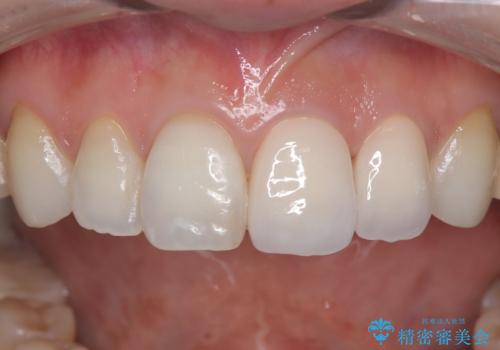

- 「前歯の色が気になる」を主訴に来院された患者さんです。以前他院にて、前歯2本をCR(プラスチック)で治療されていたところが劣化し変色していました。歯の長さも左右で異なっている状態でした。大部分がCR(プラスチック)修復されていたので、オールセラミッククラウンで治療を行いました。

古いCR(プラスチック)とその下の虫歯を除去した後に新しい土台を立てています。適合が良い被せ物を作るために拡大鏡を使用しながら歯を削り、変形のほとんどないシリコンという材料で型取りを行っています。